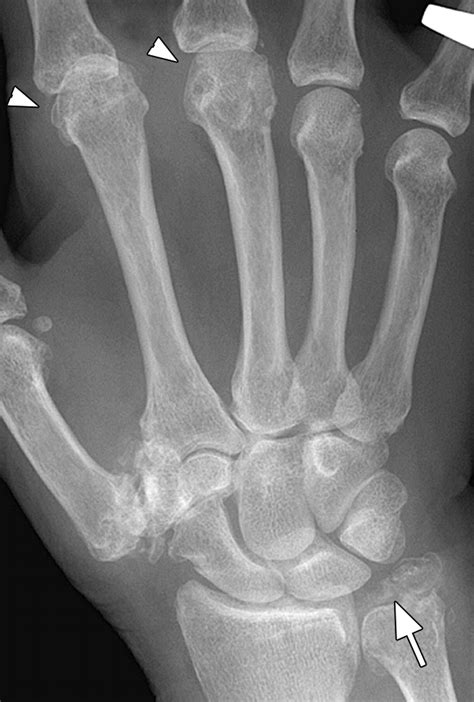

• X-rays: Standard imaging to look for joint space narrowing, bone spurs (osteophytes), and subluxation.

Thumb CMC arthritis is one of the most common causes of hand pain, particularly in women over the age of 50. The degradation of the articular cartilage leads to inflammation, pain at the base of the thumb, and eventually bone-on-bone contact, which causes significant discomfort and loss of function.

• A visible bump or “squared-off” appearance at the base of the thumb.